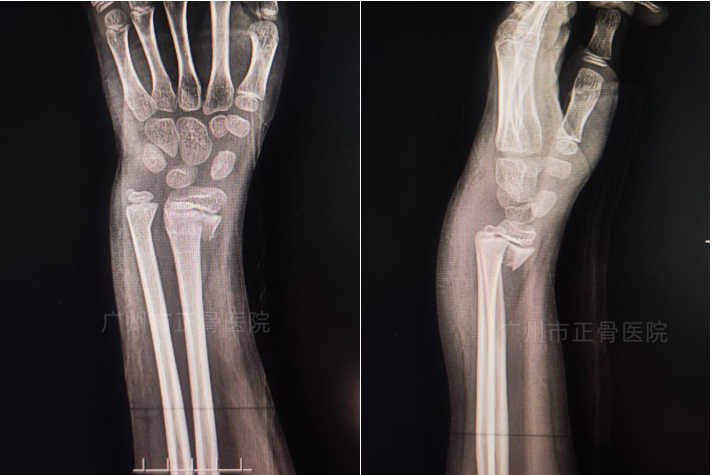

治疗:根据院桡骨远端骨折诊疗规范,予手法复位夹板外固定治疗。复位后复查X片提示骨折对位对线良好,下尺桡关节已复位,外侧加石膏托以加强固定效果,预防移位。嘱患者定期复诊换药(每周一次),指导患者适当功能锻炼。2周后复查X线提示骨折稳定,骨折线稍模糊。6周复查X线提示骨折端位线良好,骨折线已模糊,予拆除夹板,指导患者功能康复锻炼。7周后复诊,提示功能恢复正常。

▲复位后,骨折端对位对线良好